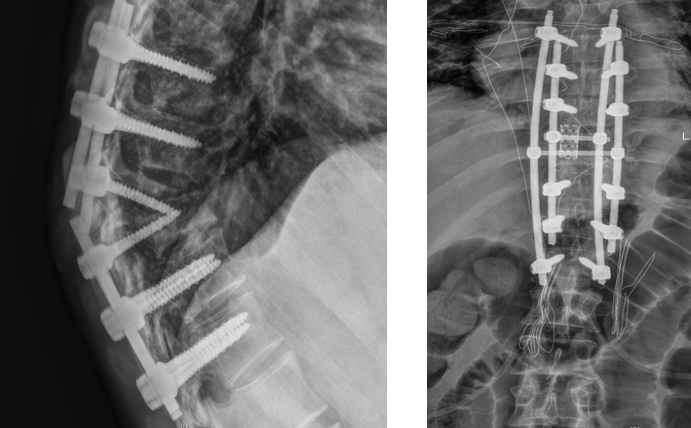

术前:内固定失效及耐药结核加剧身体畸形 术后:多重加固恢复正常脊柱曲线

“前次手术部位已经改变了原有生理组织结构,再次‘翻修’,对术者的操作水平无疑是巨大挑战,且出血风险也会加大,加上患者存在耐药结核,意味着术后并发症发生率及感染风险更高。”曾浩介绍,经过反复探讨,最后决定为患者施行胸椎后路内固定装置取出、结核病灶清除、截骨矫形、钛网植骨融合、棒系统内固定术这一手术方案,并创新性地采用四重钉棒加固手术部位,并截除部分增生病骨,达到解除患者病痛,愈后稳固、美观的手术目的。